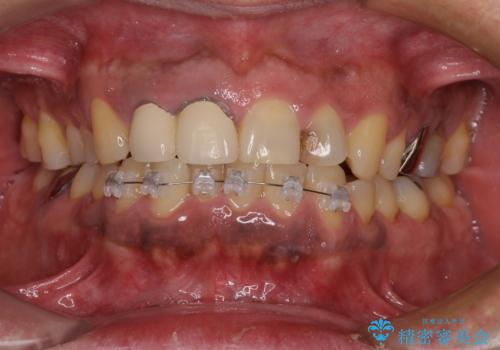

- 矯正装置

- 審美装置

- 1年4ヶ月

(2)全顎矯正歯科治療

小臼歯および親知らずの抜歯が望ましいが、患者様の希望により抜歯せずに排列へ

初診から終了まで1年3ヶ月で、特に矯正歯科治療は被せ物に換える前提であったため8ヶ月間で終了することができました。